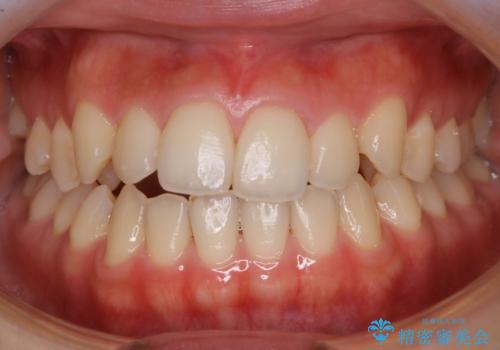

ワイヤー矯正後の後戻り 出っ歯を治したい マウスピース矯正